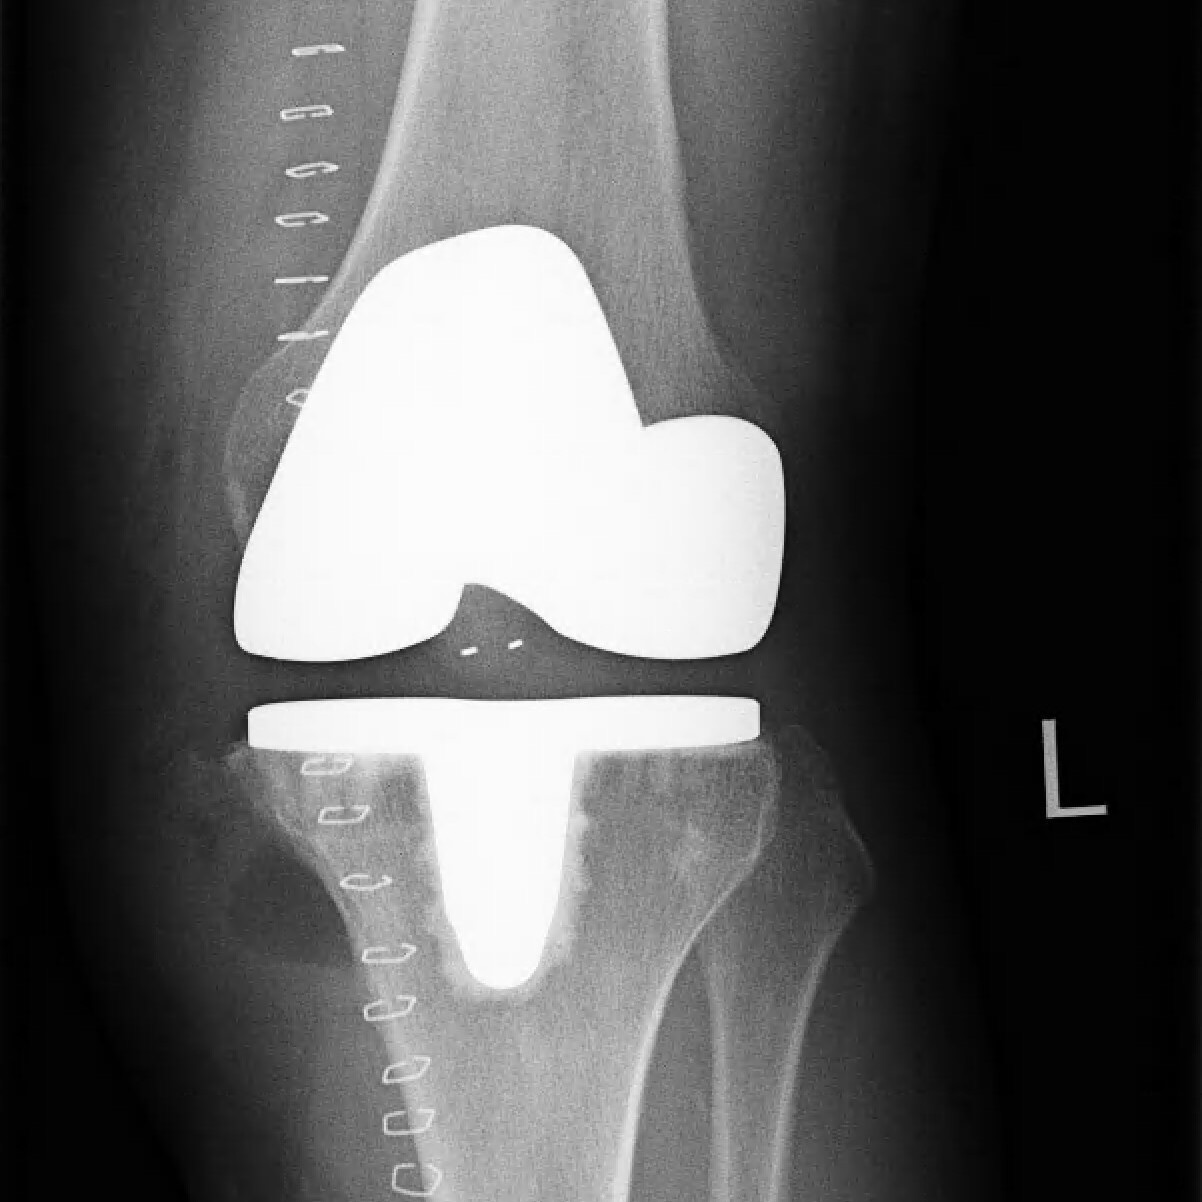

Nachdem die nicht operativen Therapiemaßnahmen (Krankengymnastik, korrigierende Einlagen, Spritzentherapie) ausgeschöpft waren und die Lebensqualität anhaltend beeinträchtigt war, wurde die Patientin über die Option eines künstlichen Kniegelenks (KnieTotalEndoProthese = KTEP) informiert. Mithilfe eines Oberflächenersatzes (Typ „Doppelschlitten“) konnte die abgenutzte Knorpeloberfläche überkront und gleichzeitig die korrekte Beinachse wiederhergestellt werden. Das Ganglion wurde über den gleichen OP-Zugang erfolgreich entfernt.

Nach erfolgter Rehabilitation (1 Woche Klinikaufenthalt, 3 Wochen Reha-Klinik und 8 Wochen ambulanter Physiotherapie) hat die Patientin in der Zwischenzeit Dank des künstlichen Kniegelenks ihr gewohntes Aktivitätsniveau im Alltag erreicht und freut sich, schon bald wieder auf dem Tennisplatz stehen zu können.